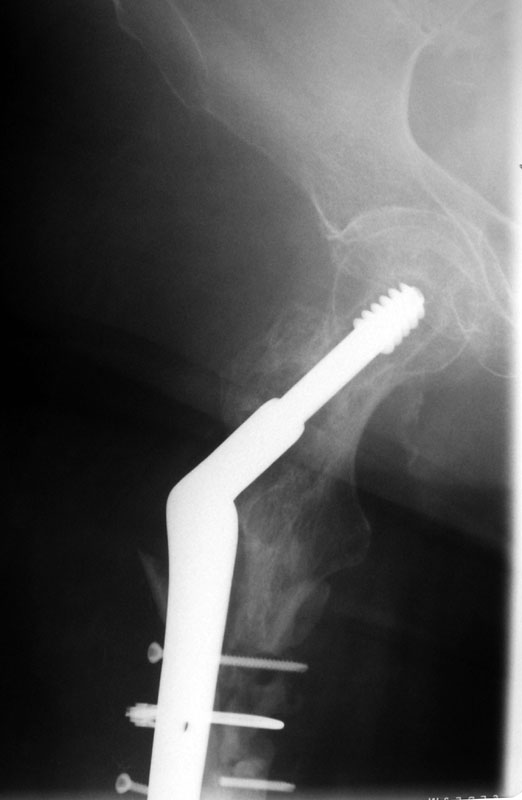

These are the Xrays of a 73 y/o women. The name of each file has the date it was taken and the view. These are all outside films and I know they are limited studies but I think the problem is evident. She had polio at age 5. 20 years ago she had a subtroch fracture plated with a DHS type implant. In Feb, 02 she presented to a local orthopod with a fracture under the plate. The hardware was loose at that time. The local orthopod kept the hardware and cabled allograft to the femur. She did well and was walking with only a cane or occ a walker until last month when she felt something was different and had some pain. She went to her orthopod who took the xrays in May. The orthopod sent her to me then. She has no motors of any significant function below the hip including lacking hip ext and flex. She has mild pain with rotational stress of the femur. She has a thick but not obese leg (she did grow up here in Wisconsin). She wears an AK brace on her leg. She has some pain but it s not too bad. She still can walk but does most of her ambulation with a wheelchair. She has little or no pain in the wheelchair. She is a 1 pack/ smoker for years. She has well controlled hypertension.

02/02/02 AP

02/02/02 lat